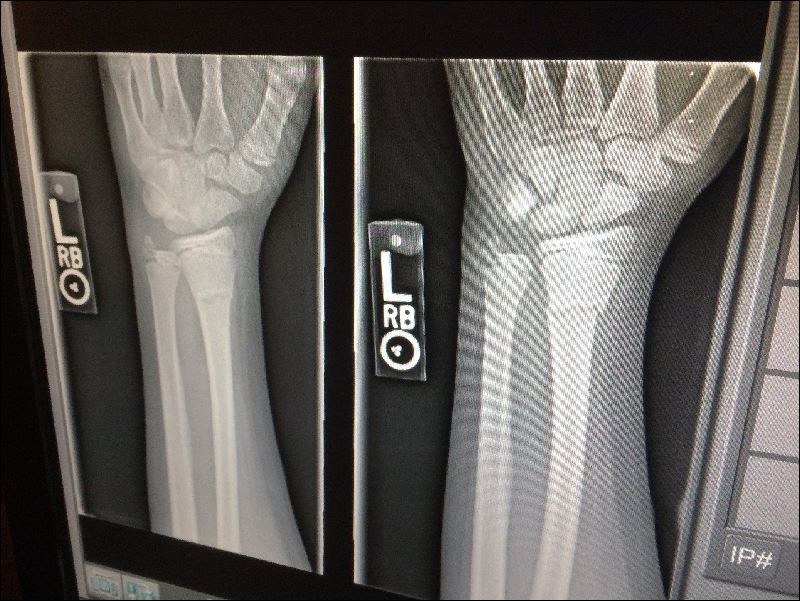

골다공증이 되어 뼈가 약해지고 등뼈가 으스러져 버리면 신장이 줄어들어 버립니다.

일단 척추 골절이 발생하면 재골절의 위험이 더 높아지게 됩니다.

신경이 쓰이는 증상이 있으면 그대로 두지 말고 빨리 의료 기관에서 진찰을 받읍시다.

4cm 이상 신장이 줄어든 사람은 적극적으로 골밀도 검사나 엑스레이 검사를 받도록 권장하고 있습니다.